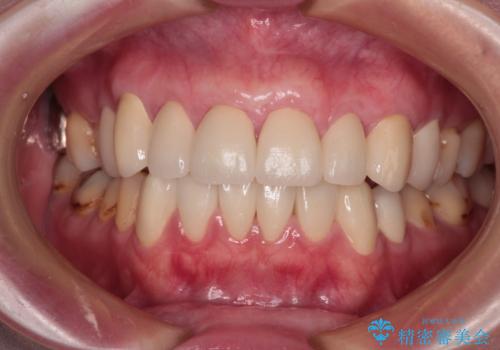

歯肉移植術による根面被覆を行うかどうかは非常に悩まれていましたが、歯肉が覆われたことで長く見えていた歯の長さが整い、きれいな前歯の仕上がりとなりました。